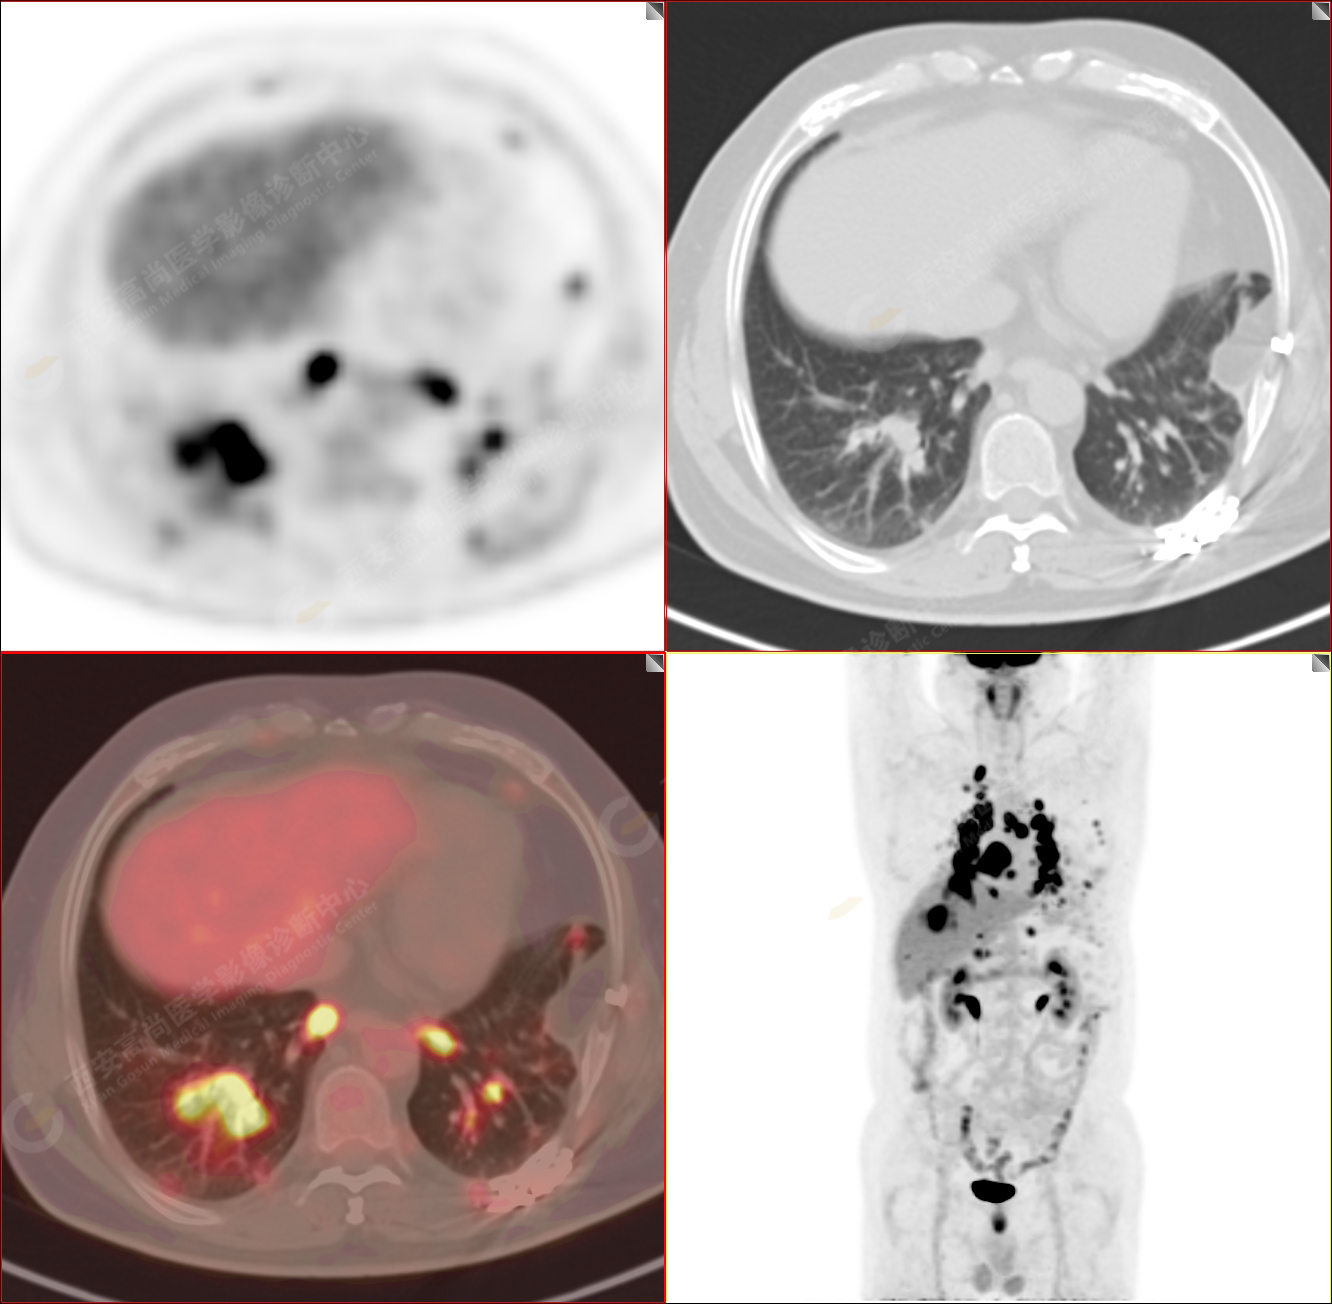

PET/CT-MR診斷結(jié)節(jié)病雙肺及全身多發(fā)淋巴結(jié)廣泛累及1例【西安高尚病例】

男性,53歲,頭暈半月入院,CT發(fā)現(xiàn)肺內(nèi)腫塊,雙肺多發(fā)大小不等實(shí)性及粟粒樣結(jié)節(jié),雙肺門(mén)及縱隔多發(fā)腫大淋巴結(jié)。病程中無(wú)發(fā)熱、胸悶氣及胸部不適。既往:左側(cè)肋骨外傷史。

PET/CT圖像